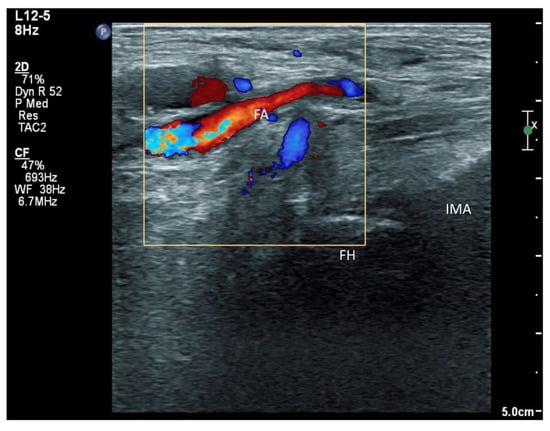

In addition to the classical PENG injection, our modified approach highlighted the addition of pericapsular infiltration in the iliopsoas plane to cover the low articular branch of the femoral nerve and a sagittal approach to target the ONAB. The algorithm was still used to perform diagnostic blocks, followed by alcohol neurolysis 10 min later for those with a positive diagnostic block in the same setting under real-time ultrasound guidance (Philips Affiniti 70, 5–12 MHz linear probe or 1–5 Hz curved probe depending on the depth of the target). In the modified approach, the procedure consisted of 3 needle insertions with the use of 22-gauge 10 cm Quincke needles. The first needle for the high femoral nerve articular branches (high FNAB branches) and AON was inserted in the same way as the PENG approach between the anterior inferior iliac spine (AIIS) and the iliopubic eminence (IPE) deep to the psoas tendon (Figure 2 and Figure 3). A second needle for the low branches of FNAB was inserted in-plane from lateral to medial and advanced through the sartorius, rectus femoris and iliopsoas muscles. The final needle position was in the plane superficial to the iliofemoral ligament medial to the rectus femoris tendon over the femoral head (Figure 4 and Figure 5). The third injection for the obturator nerve articular branches was used to target the caudal aspect of the inferomedial acetabulum (IMA) by scanning in a sagittal plane with a caudal-to-cephalad needle trajectory. The precise localization of the caudal aspect of the IMA could be first approached via the ordinary way (an oblique scan) as described in our first case series [5]. The probe was slowly rotated obliquely until the acetabulum, femoral head, and neck were aligned in the same plane, with the superomedial acetabulum coming into view. The probe was then slid caudally with the end point being the presence of the acetabulum without the femoral head. This referred to the location of the inferomedial acetabulum. The probe was then adjusted until the IMA was in the middle of the image, followed by rotating the probe by approximately 60 degrees (Figure 6). In this scan, the pectineus, the caudal aspect of the IMA and, occasionally, the obturator externus were seen. The ONAB could be visualized in the wedge of the subpectineal space directly adjacent to the IMA. Before any needle insertion, the probe was tilted slightly medially towards the obturator foramen to look for the acetabular/posterior branch of the obturator vessels which are usually deeper than the ONAB. The needle was then inserted from caudal to cephalad in-plane until the needle tip reached the wedge space consisting of the ONAB (Figure 7). In case the wedge space could not be clearly visualized, the needle tip would then be advanced until touching the caudal bony surface of the IMA directly underneath the pectineus. Then, 0.5–1% ropivacaine (4, 3 and 2 mL, respectively) was injected into the above three landmarks. The needles were left in situ during the diagnostic test while their positions were reconfirmed by ultrasound before 100% alcohol was injected into the above targets with volumes in a 1:1 ratio between alcohol and local anaesthetics. A decrease of ≥50% in composite pain score on hip flexion at 45 degrees 10 min after the blocks signified a positive diagnostic block. As a post-neurolysis routine manner, stylets were reinserted before needle withdrawal.

Figure 3. Ultrasound image showing injection of FNAB and AON by infiltration of the drug between the IPE and AIIS from lateral to medial (PENG approach). FA: femoral artery, AIIS: anterior inferior iliac spine, IPE: iliopectineal eminence, *: absolute alcohol spreading underneath iliopsoas muscle above the ASIS-IPE bone surface, white arrow: needle.

Figure 8. Doppler signal of the femoral artery and its branches when scanning the inferomedial acetabulum by the classical oblique approach. FH: femoral head, FA: femoral artery and branches, IMA: inferomedial acetabulum.